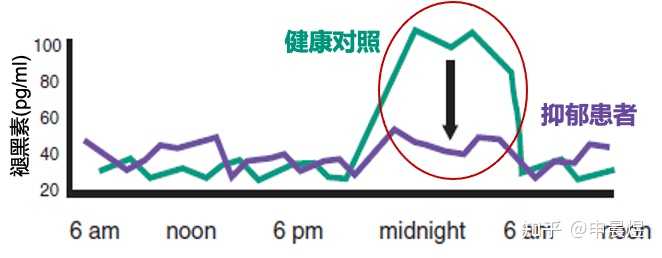

抑郁症可致生物节律相位延迟

抑郁患者的生物节律往往是相位延迟的,意味着早上觉醒度不足,晚上入睡困难。难以入睡进一步加剧了白天的困倦感[7]。

抑郁症患者的睡眠结构节律紊乱[8]